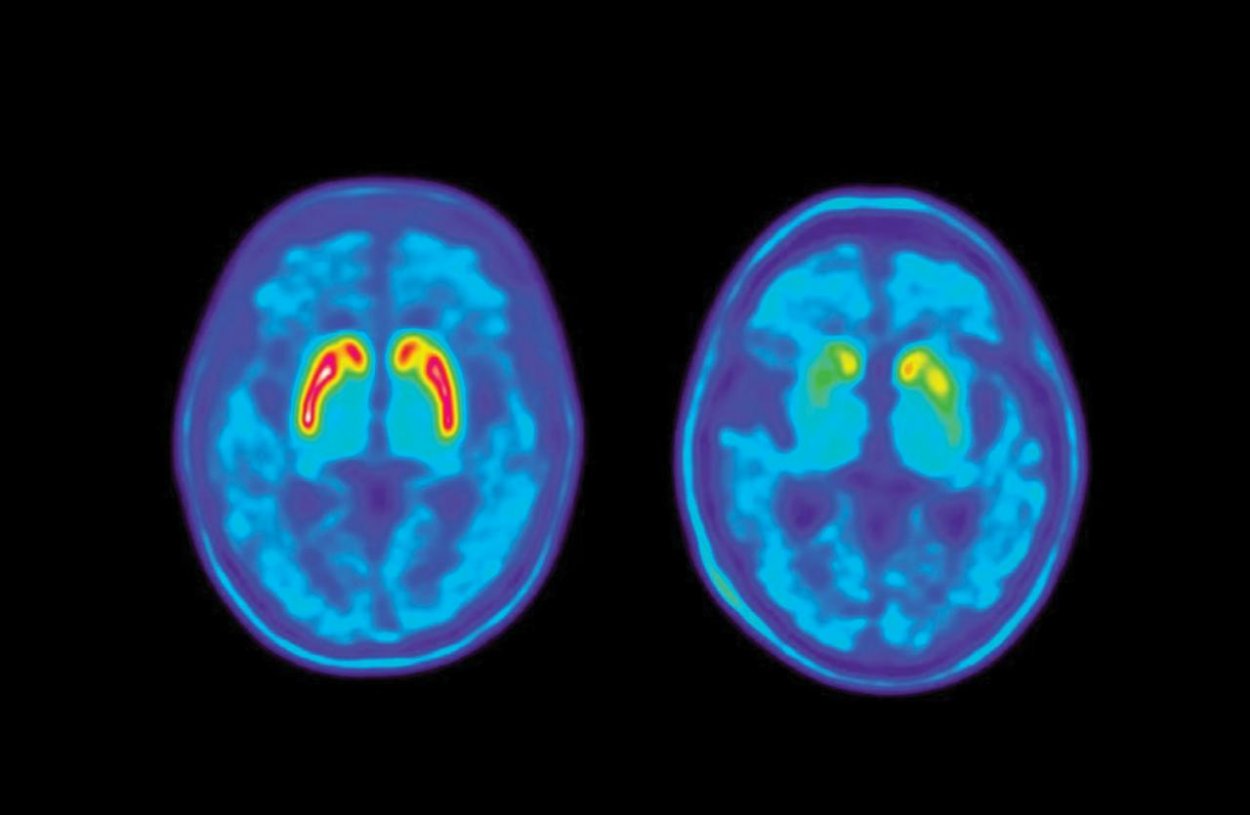

Servis mozgu pri Parkinsonovej chorobe WIKIMEDIA COMMONS/JAKOBSON MO ET AL. Porovnanie PET snímky mozgu zdravého človeka a pacienta s Parkinsonovou chorobou, u ktorého je viditeľný pokles dopamínového signálu.

moderná terapia ponúka pacientom s Parkinsonovou chorobou pomerne široké spektrum možností. Avšak ich mechanizmus účinku je v mnohých ohľadoch podobný. Charakteristickým znakom ochorenia je úbytok nervových buniek, ktoré produkujú dopamín. Je to komunikačná látka zohrávajúca významnú úlohu v procese mozgového klebetenia. Dopamín produkuje niekoľko malých skupín nervových buniek, ktoré dohliadajú na prácu iných neurónov.